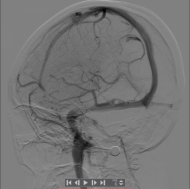

右侧大脑中动脉慢性闭塞再通前后对比图